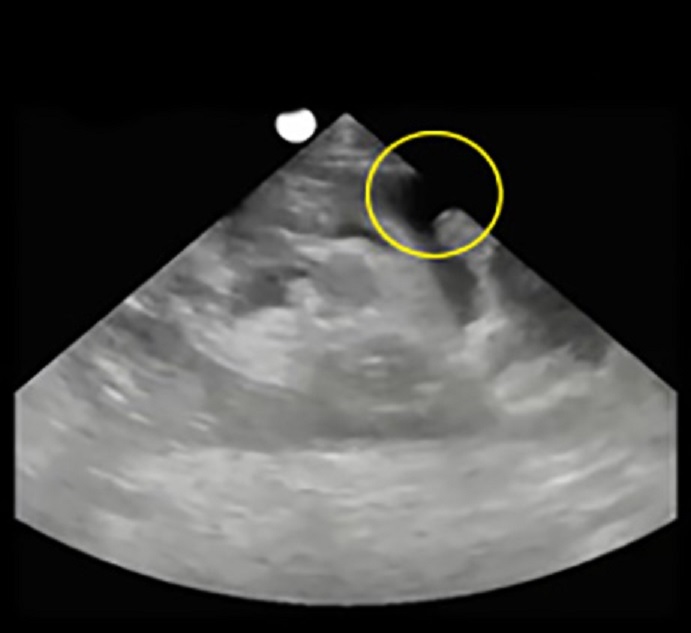

Image - Petite quantité d'ascites

Entourés : Ascites